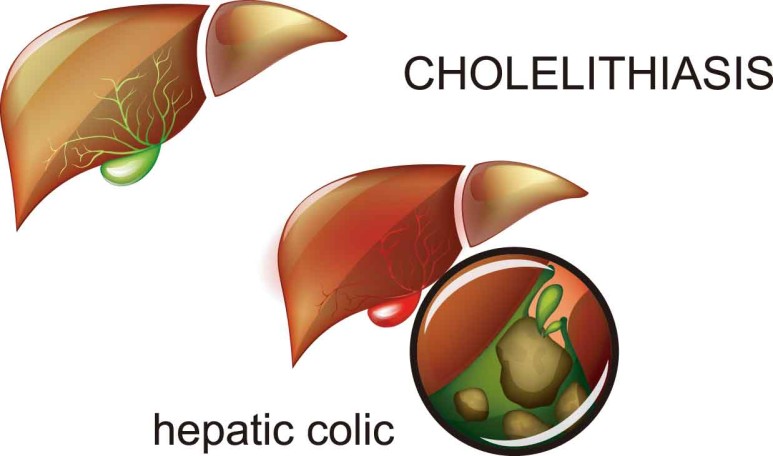

배쇄성 황달이 발생하는 원인은 다양한 총담관석, 담관협착, 담관 내 기생충,

Mirizzi 증후군, 원발성 경화 담관염, 췌장염, 혈액 담즙증 등을 들 수 있습니다.

그 원인이 총 담관 담석의 경우 담낭 확장이 이루어지지 않는 경우가 많은데 이는 완전 폐쇄가 아닌 부분 폐쇄로 담즙이 부분적으로 흘러나와 담낭 내의 압력을 높이지 않기 때문입니다.

또한 총 담관 담석의 유래가 담낭인 경우에는 담낭에 만성적인 염증이 동반되어 섬유화가 진행되어 담낭의 확장이 불가능하기 때문입니다.

따라서 신체검진시 손으로 만질수록 담낭의 크기가 커지고 있으나 압통이 없는 경우에는

이를 Courvoisier 징후라고 하는데, 담관폐쇄의 원인이 총담관석에 의한 것이 아니라 악성폐쇄일 가능성이 높습니다.